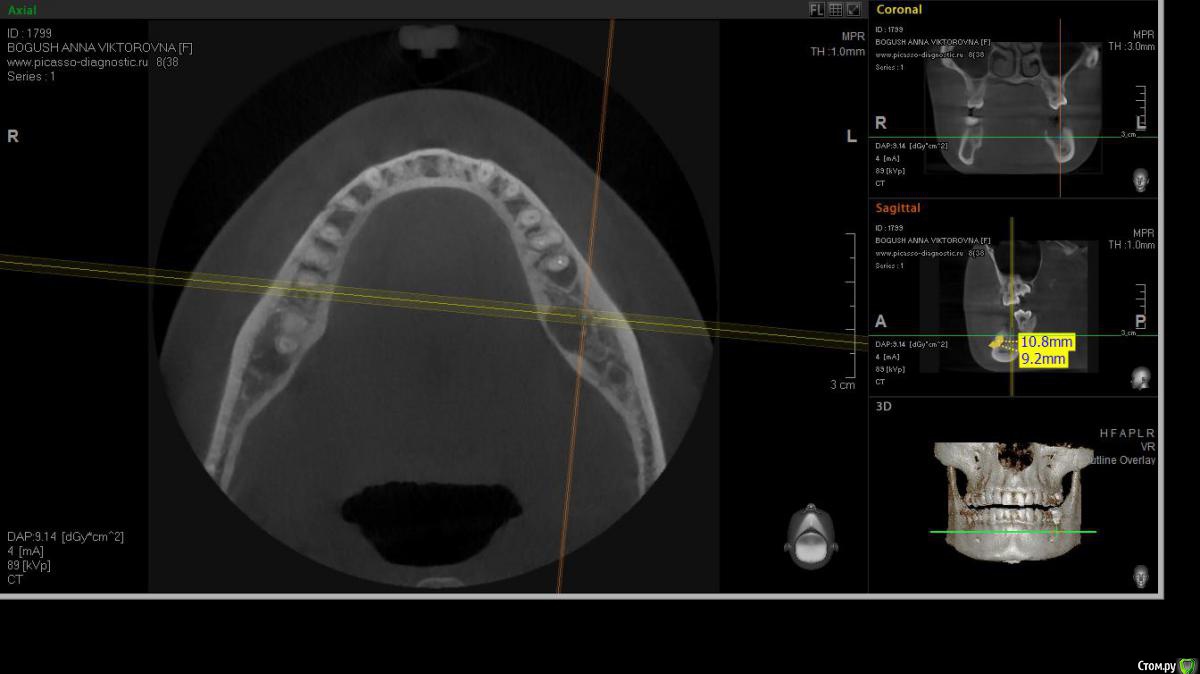

cor Опубликовано 2 апреля, 2016 Поделиться Опубликовано 2 апреля, 2016 Доброго времени суток, коллеги! Каков Ваш прогноз? Удалять пац. совсем не хочет(знакомая). Есть хоть какая то вероятность, что ретрит поможет? <script> </script> Ссылка на комментарий

cor Опубликовано 2 апреля, 2016 Поделиться Опубликовано 2 апреля, 2016 (изменено) гадская вирусятина на компе мешает. Нет конечно желающих. Но если ретрит будет, то делать его буду я. Но слабо верю в положительный исход(( Изменено 2 апреля, 2016 пользователем cor Ссылка на комментарий

Гарриевич Опубликовано 3 апреля, 2016 Поделиться Опубликовано 3 апреля, 2016 Доброго времени суток, коллеги! Каков Ваш прогноз? Удалять пац. совсем не хочет(знакомая). Есть хоть какая то вероятность, что ретрит поможет? шансов не меньше чем тут Ссылка на комментарий

St. Опубликовано 3 апреля, 2016 Поделиться Опубликовано 3 апреля, 2016 Доброго времени суток, коллеги! Каков Ваш прогноз? Удалять пац. совсем не хочет(знакомая). Есть хоть какая то вероятность, что ретрит поможет? Вполне есть смысл попробовать. Вероятность есть, только "заживать" будет долго. Ссылка на комментарий

cor Опубликовано 5 апреля, 2016 Поделиться Опубликовано 5 апреля, 2016 Почему?Наверное потому что такие объемные очаги ещё не перилечивал. Но деваться некуда, будем пробовать. Ссылка на комментарий

Л Ю С Я Опубликовано 5 апреля, 2016 Поделиться Опубликовано 5 апреля, 2016 Наверное потому что такие объемные очаги ещё не перилечивал. Но деваться некуда, будем пробовать.Уже не раз писали, что размер не имеет значения)))). Не надо перелечивать очаг. Ваша задача пройти, правильно сформировать, очистить и запаковать каналы, а также правильно восстановить коронковую часть. И будет вам хилинг))) 2 Ссылка на комментарий